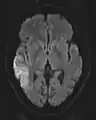

The most common application of conventional DWI (without DTI) is in acute brain ischemia. DWI directly visualizes the ischemic necrosis in cerebral infarction in the form of a cytotoxic edema,[38] appearing as a high DWI signal within minutes of arterial occlusion.[39] With perfusion MRI detecting both the infarcted core and the salvageable penumbra, the latter can be quantified by DWI and perfusion MRI.[40]

DWI showing necrosis (shown as brighter) in a cerebral infarction